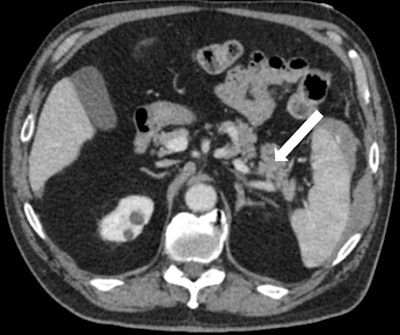

After initial resuscitation and focused assessment with sonography in trauma (FAST), he underwent a CT of the chest, abdomen, and pelvis that revealed a 1.4-cm grade III splenic laceration near the anterior lip associated with a focus of contrast extravasation. The exam also revealed an associated subcapsular hematoma larger than 50% of the surface area of the spleen, with hemorrhage tracking along the left paracolic gutter into the pelvis (figures 1A and 1B). The pancreas appeared unremarkable on this CT (figure 2).